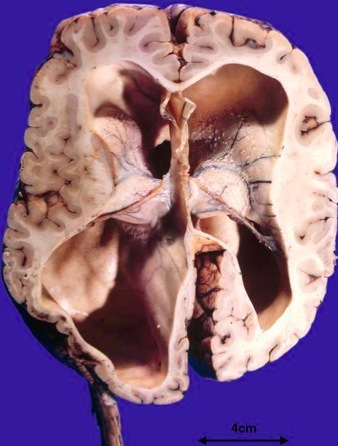

Hydrocephalus

Etiopath:

Sx: headache, vomiting worse in morning & triad of nl hydrocephalus (urinary incontinence, gait instability, dementia)

Sx in children: bulging frontal bone, sunsetting eyes (downward deviation)